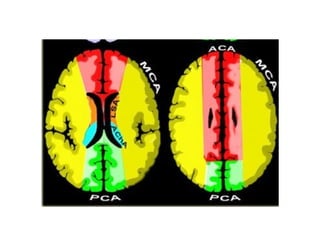

• Watershed:

– Look at watershed and border zone areas

– Hypo-perfusion

• Location – watershed pattern

Case 4

• 56 year old female who upon waking post-op after elective

surgery was found to have L sided weakness and neglect

• History of HTN

• Meds - Lisinopril

• BP- 132/74, P– 84

• General exam: Unremarkable, RRR

• NEURO EXAM:

- Left face, arm, and leg weakness

- Neglect

- DTR’s brisk on the left, toe up on left

• Right hemisphere watershed infarct secondary to

hypoperfusion in the setting of Right ICA stenosis

• On review of anesthesia records, blood pressure dropped to

82/54 during the procedure

• Patient was discharged to in-patient rehab

Answer